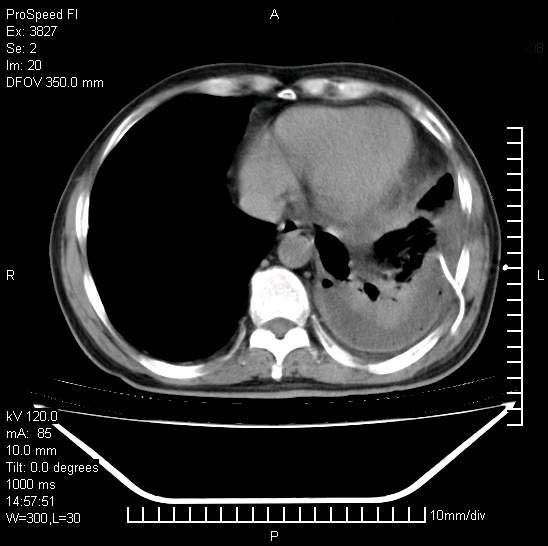

男性,一月前出现右侧肋区疼痛,较剧烈,干咳,无发热,自诉使用抗炎药后缓解,几天前又出现左侧剧烈疼痛,

发热,体温38。9,今天ct,考虑左侧包裹性脓胸,胸腔积液,右上中肺小斑片影,结核/炎症?胸水未见恶性细胞。

左侧肺脓疡,化脓性胸膜炎(脓胸),不支持结核诊断,建议继续抗感染治疗

支持左侧肺脓肿并脓胸,肺内炎症,建议继续抗炎治疗后复查。

脓胸没问题,肺内还可见感染灶,感觉不像是结核性病变.